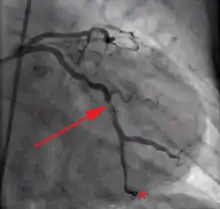

- coronary angiography